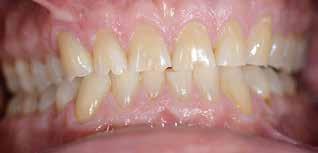

PATIENTTILFÆLDET

En 40 år gammel mand henvendte sig med bekymring for både æstetik og symptomer fra tænderne (Fig. 1). Han fortalte, at

Præoperativ status

Fig. 1. 40-årig sund og rask mand møder bekymret for sine slidte tænder. Klinisk ses frakturer og substanstab langs incisalkanterne på overkæbetænderne.

Fig. 1. A 40-year-old healthy man is concerned for his worn teeth. Clinically, fractures and loss of tooth substance are observed at the incisal edge of the upper front teeth.

Okklusalt billede af A) over- og B) underkæbe

2. Klinisk ses tydelig slitage ind i dentinen på samtlige tænder fra 6’er til 6’er i begge kæber.

Fig. 2. Clinically, extensive wear into the dentin of all teeth in both jaws is observed.

Klinisk undersøgelse viste et tandsæt med enkelte restaureringer, men med slitagedefekter okklusalt/incisalt på samtlige tænder fra 6’er til 6’er i over- og underkæbe (Fig. 2). Defekterne strakte sig tydeligt ind i dentinen. Baseret på anamnesen og de kliniske fund blev erosion set som hovedårsagen til tandsliddet, mens attrition formodedes at være en medvirkende faktor.